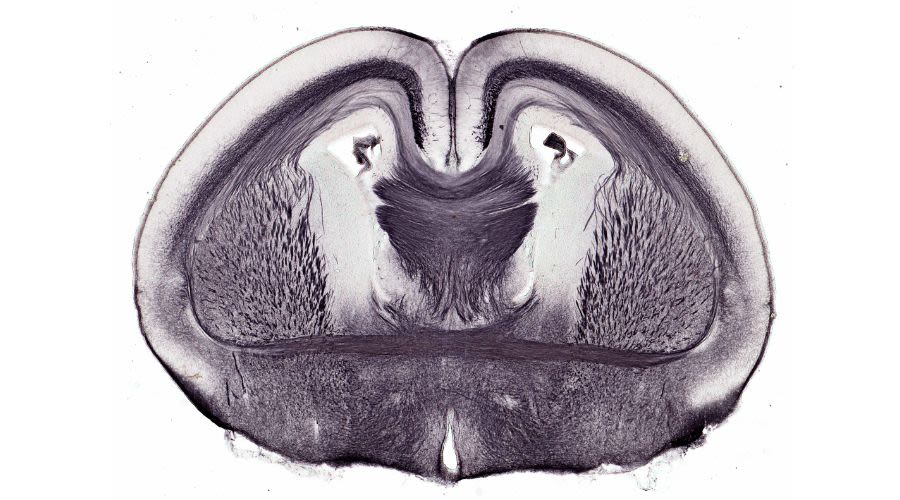

Dormant stem cells in the hippocampus can be activated to produce new nerve cells

With ageing, the production of new neurons greatly diminishes in human and mouse brains, and I wondered why. To our surprise, we found the stem cells in the brains of older animals had become dormant. In 2008, we discovered these cells could be stimulated in vitro to produce new neurons. Later, in 2012, we showed stem cells could be activated in aged mice through exercise, which, excitingly, led to learning and memory improvements. An ongoing human study of the effects of exercise also shows evidence of significantly improved cognition, suggesting a similar mechanism exists in people.

Exercise can activate dormant stem cells in the brains of older animals